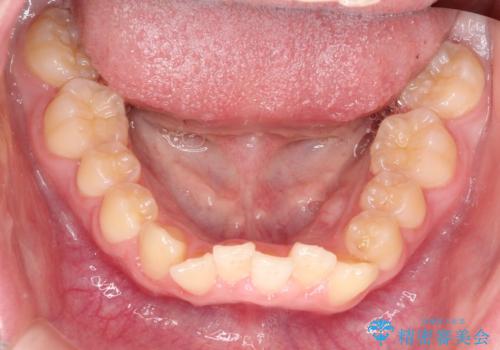

なるべく通院回数を減らして矯正したい インビザラインでのガタガタ矯正

- 上下の歯並びを治したいとのことで来院されました。

受験生ということもあり、なるべく通院回数を減らしての矯正を希望されたので、インビザラインで治療をすることにしました。